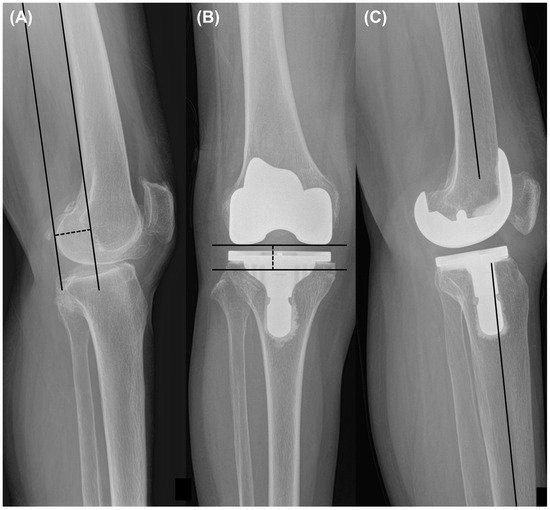

The radiographs obtained before and two years after the surgery were analyzed. The analysis involved measuring the Hip-Knee-Ankle (HKA) angle, which is the angle formed between the line connecting the center of the femoral head to the center of the knee and the line from the center of the knee to the center of the talus, using whole-leg standing radiographs. Varus and valgus were designated as positive and negative HKA angles, respectively [16]. Additionally, the lateral distal femoral angle (LDFA) and medial proximal tibial angle (MPTA) were assessed to examine the preoperative phenotype and implant position in the coronal plane [17,18]. The LDFA was defined as the angle between the line parallel to the femoral condyle and the mechanical axis of the femur. The MPTA was defined as the angle between the line parallel to the tibial plateau or component and the anatomical axis of the tibia (Figure 1). Knee preoperative phenotypes were classified as previous investigation [19]. Alignment variation was defined as a 3° range for any of these angles. The mean values of these phenotypes represented 3° increments in the angle, starting from the overall mean value observed in a young non-osteoarthritic population (NEUHKA0° = 0°, NEULDFA0° = 87°, NEUMPTA0° = 87°). The nomenclature of the phenotypes was constructed as follows: the first part (NEU, VAR, and VAL) indicated the alignment direction; the second subscripted part (HKA, LDFA, and MPTA) represented the measured angle, and the last part (0°, 3°, 6°, etc.) indicated the mean deviation of the phenotype from the mean value. Postoperative HKA angle outliers were defined as greater than 3° or less than −3°, and LDFA or MPTA outliers were defined as greater than 93° or less than 87°, as described in a previous study [20]. The distribution rates of the HKA, LDFA, and MPTA phenotypes were compared between the two groups. Correlation analysis was performed for the preoperative HKA angle and other pre- and postoperative variables, including LDFA, MPTA, tibial slope, femoral condylar offset, joint line distance, and femoral component rotation angle. The tibial slope was quantified as the angle formed between the mid-diaphysis line of the tibia and the line representing the posterior inclination of the tibial plateau or implant in the lateral view.

Figure 1.

Measurement included (A) hip-knee ankle (HKA) angle, (B) lateral distal femoral angle (LDFA) and medial proximal tibial angle (MPTA) on whole-leg standing radiographs, and (C) tibial slope on lateral view radiographs.